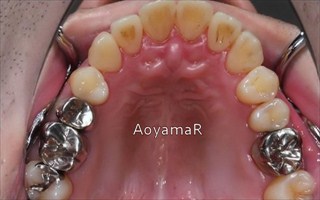

下顎前突(反対咬合、上あごの劣成長等を含む)の矯正症例

下顎前歯1本抜歯による上下前歯のバランスの改善

マウスピース型カスタムメイド矯正装置(インビザライン)単独による治療

治療前